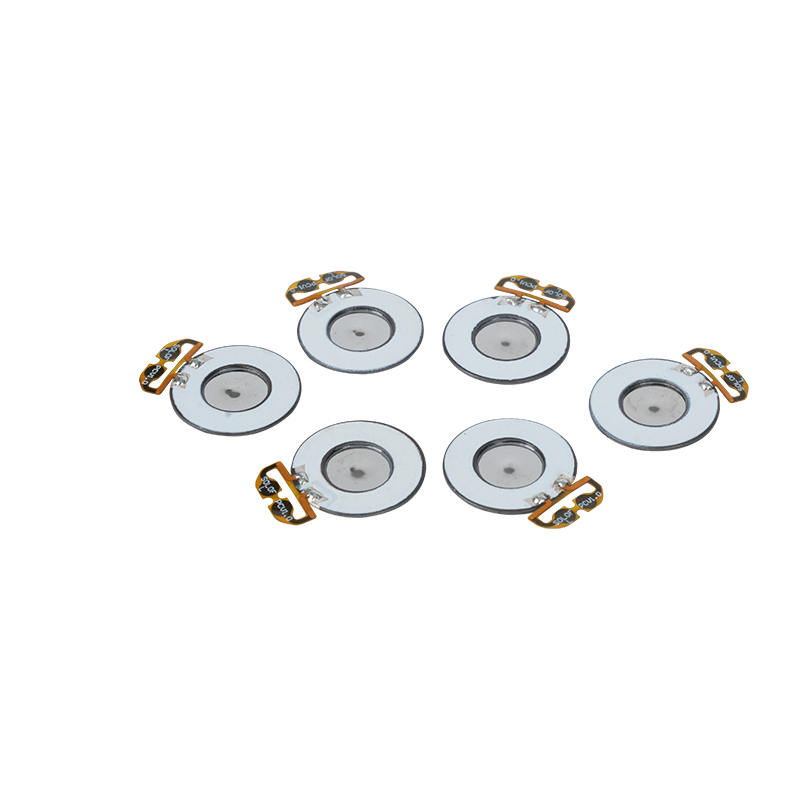

মেডিক্যাল মেশ নেবুলাইজার ট্যাবলেটগুলি হল শ্বাস-প্রশ্বাসের মাধ্যমে বিভিন্ন শ্বাসযন্ত্রের ব্যাধি যেমন হাঁপানি, এবং দীর্ঘস্থায়ী অবস্ট্রাকটিভ পালমোনারি ডিজিজ (সিওপিডি) ইত্যাদির চিকিৎসার জন্য ওষুধ বা দ্রবণকে ক্ষুদ্র অ্যারোসল কণাতে রূপান্তর করতে মেডিকেল ডিভাইসে ব্যবহৃত নির্ভুল উপাদান। নেবুলাইজার শীটের নকশা এবং উপাদান নির্বাচন কার্যকর ওষুধ সরবরাহ এবং রোগীর আরাম নিশ্চিত করার জন্য গুরুত্বপূর্ণ। স্টেইনলেস ডায়াফ্রাম শীটটি একটি নির্ভুল লেজার প্রক্রিয়ায় লেজার ড্রিলিং প্রযুক্তির মাধ্যমে ইস্পাত শীটে হাজার হাজার ক্ষুদ্র 2-3μm জালের ছিদ্র দিয়ে পাঞ্চ করা হয় এবং তারপরে এটি পিজোইলেকট্রিক সিরামিক রাউন্ড শীটের সাথে শক্তভাবে বন্ধন করা হয়, যা পাইজোইলেকট্রিক শীটের রেজোন্যান্ট ফ্রিকোয়েন্সিকে পিসি-ইলেকট্রিক শীট-এর মাধ্যমে উচ্চ শক্তির শক্তিতে রূপান্তরিত করে। বোর্ড, এবং দ্রুত ভেঙ্গে যায় তরল ওষুধ সূক্ষ্ম অ্যারোসল কণাতে। এই ফোঁটাগুলিকে মাঝারি কণার আকারও বলা হয়, যখন মাঝারি কণার আকার D50 শতাংশ> 60% বা তার বেশি পৌঁছায়, তখন কণাগুলি ফুসফুসের গভীরে অ্যালভিওলির পৃষ্ঠে শ্বাস-প্রশ্বাসের সাথে পৌঁছানোর জন্য যথেষ্ট ছোট হবে, এইভাবে ওষুধের শোষণের দক্ষতা এবং থেরাপিউটিক প্রভাবকে উন্নত করবে। মেডিকেল মেশ মাইক্রো মেশ নেবুলাইজার শীটে প্রধানত বিভিন্ন ফর্ম বিদ্যমান, স্টেইনলেস স্টীল মাইক্রো জাল নেবুলাইজার শীট, নিকেল প্যালাডিয়াম মেডিকেল নেবুলাইজার শীট, পিআই পলিমার মেডিকেল নেবুলাইজার শীট এবং আরও অনেক কিছু। উপরের সবগুলোই পাইজোইলেকট্রিক সিরামিক কম্পন শক্তি রূপান্তরের মাধ্যমে পরমাণুকরণ প্রভাব অর্জন করে।

Polyimide (Polyimide) PI হিসাবে উল্লেখ করা হয়, জৈব পলিমার উপকরণের সর্বোত্তম ব্যাপক কর্মক্ষমতা, এটির চমৎকার রাসায়নিক স্থিতিশীলতা রয়েছে এবং পরমাণুযুক্ত ট্যাবলেটগুলির কার্যকারিতা দীর্ঘমেয়াদী ব্যবহার নিশ্চিত করতে বিভিন্ন ধরণের ওষুধের ক্ষয় সহ্য করতে পারে। উপরন্তু, পলিমার PI ফিল্মের তাপীয় স্থিতিশীলতাও চমৎকার, তাপমাত্রা পরিসীমা -200 ~ 300 ° C, উচ্চ নিরোধক, পরিবেশগত সুরক্ষা এবং অ-বিষাক্ততার দীর্ঘমেয়াদী ব্যবহার সহ, একটি বিশেষ প্রকৌশল উপাদান হিসাবে, মহাকাশ মাইক্রোইলেক্ট্রনিক্স ন্যানো-তরল ক্রিস্টাল বিভাজন ক্ষেত্রের মেম্বার অন্যান্য শতাব্দীর অন্যতম এবং অন্যান্য দেশের অন্তর্ভুক্ত ছিল। সবচেয়ে প্রতিশ্রুতিশীল প্রকৌশল উপকরণ, এবং এটি সহজ নয় উচ্চ-তাপমাত্রা নির্বীজন প্রক্রিয়ার মধ্যে বিকৃত করা, পণ্য পুনরায় ব্যবহার করা হয় তা নিশ্চিত করতে! যৌনতা এবং নিরাপত্তার জন্য, আমরা লেজারের ছিদ্রের জন্য লেজার প্রযুক্তি ব্যবহার করি, স্টেইনলেস স্টীল এবং পাইজোইলেকট্রিক শীটের মধ্যে ইমপ্লান্ট করা PI ফিল্ম, পাইজোইলেকট্রিক সিরামিক অতিস্বনক প্রযুক্তির ব্যবহার যাতে PI ফিল্মের মাধ্যমে পরমাণুযুক্ত ফোঁটাগুলি 3 ~ 4 μm কণার পরমাণুকরণে বিচ্ছুরিত হয়, মেডিক্যাল নেবুলাইজেশনের ব্যবহারকারীদের নিরাপত্তার জন্য মেজর নেবুলাইজেশন, মেডিক্যাল নেবুলাইজেশন তৈরি করে। PI এর সাথে নন-ক্লগিংয়ের প্রধান সুবিধা, গর্তের ভেতরের প্রাচীরটি মসৃণ এবং বৃত্তাকার, তরলের কোন অবশিষ্টাংশ নেই, সূক্ষ্ম এবং স্থিতিশীল এর পরমাণুকরণ। পরমাণুকরণ সূক্ষ্ম এবং স্থিতিশীল। পিআই ফিল্ম নেবুলাইজার ট্যাবলেট এটি কার্যকরভাবে ওষুধের অবশিষ্টাংশ প্রতিরোধ করতে পারে, ক্রস-দূষণের ঝুঁকি কমাতে পারে। ব্যবহারিক প্রয়োগে, পলিমার PI মেমব্রেন নেবুলাইজার ট্যাবলেটগুলির কম শক্তি খরচের বৈশিষ্ট্যগুলিও প্রতিফলিত হয়েছে, সংক্ষেপে, পলিমার PI মেমব্রেন নেবুলাইজার ট্যাবলেটগুলি এর চমৎকার কার্যকারিতা এবং ডিজাইনের সুবিধা সহ, মেডিকেল নেবুলাইজেশন থেরাপির ক্ষেত্রে একটি অপরিহার্য অংশ হয়ে উঠেছে৷

সীসা-মুক্ত পাইজোইলেকট্রিক সিরামিকগুলি পাইজোইলেকট্রিক শিল্প "মুক্তা" হিসাবে পরিচিত, ভবিষ্যত ধীরে ধীরে সমস্ত দিকগুলিতে সীসা-ভিত্তিক পাইজোইলেকট্রিক সিরামিকগুলিকে প্রতিস্থাপন করবে, যার ইতিমধ্যেই একই পাইজোইলেকট্রিক কর্মক্ষমতা এবং সীসা-ভিত্তিক পাইজোইলেকট্রিক শীট রয়েছে। এটি সম্পূর্ণরূপে অ-বিষাক্ত, নিরীহ, নিরাপদ এবং পরিবেশগতভাবে বন্ধুত্বপূর্ণ, এতে সীসা, অ্যান্টিমনি এবং অন্যান্য ভারী ধাতু এবং অন্যান্য রোহস-সীমাবদ্ধ উপাদান নেই, উচ্চ কিউরি তাপমাত্রা Tc-328 ° C, খুব কম বৈদ্যুতিক ক্ষতি TangentLoss অতএব, সীসা-মুক্ত পাইজোইলেকট্রিক মেডিকেল অ্যাটোমাইজেশন চিপের দুর্দান্ত বাণিজ্যিক মূল্য এবং সর্বজনীন মূল্য রয়েছে, সত্যিকারের অ-বিষাক্ত এবং পরিবেশগতভাবে বন্ধুত্বপূর্ণ, সীসা-মুক্ত পাইজোইলেকট্রিক সিরামিক ছাড়াও দূষণকারী নয়, সীসা-ভিত্তিক সিরামিকের সাথে সামঞ্জস্যপূর্ণ পাইজোইলেকট্রিক কর্মক্ষমতা, একটি জনপ্রিয় পরিবেশ বান্ধব পাইজোইলেকট্রিক সিরামিক হয়ে উঠবে। বছরের পর বছর গবেষণা এবং উন্নয়নের পর, ক্রমাগত পরীক্ষা এবং পরীক্ষা-নিরীক্ষার পর, কোম্পানিটি সীসা-ভিত্তিক পরমাণুকরণ চিপের মতো একই পরিমাণ পরমাণুকরণ এবং একই ব্যাসের কণার প্রয়োজনীয়তা অর্জনের জন্য সীসা-মুক্ত মেডিকেল অ্যাটোমাইজেশন চিপ তৈরি করতে সফল হয়েছে। সীসা-মুক্ত মেডিকেল মেশ নেবুলাইজার চিপ, অবশ্যই চকচকে হবে এবং বিস্তৃত পরিসরের ব্যবহারের পরিস্থিতি পাবে।